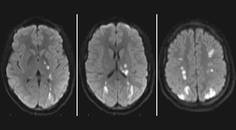

CADASIL Misdiagnosed as Multiple Sclerosis